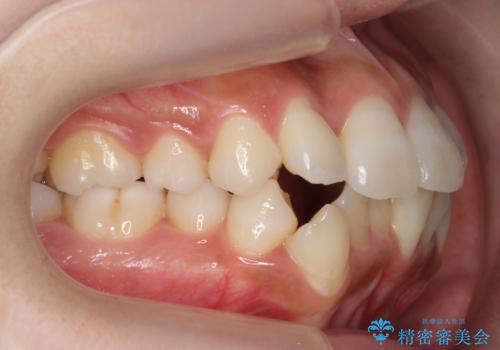

犬歯が歯ぐきにうまっている 真ん中のずれ、出っ歯を治したい

- 出っ歯を主訴に来院。

右上の犬歯が内側に生えていました。

右上の半分埋まっている犬歯を抜歯し、残り上下左右3本抜歯してワイヤー矯正を行いました。